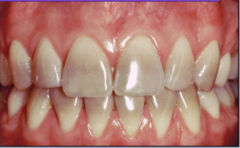

Staining that may occur from enlarged pulp chamber or trauma (darkened dentin)

Front

Intrinsic stain- endogenous ex. tetracyline stain

Back